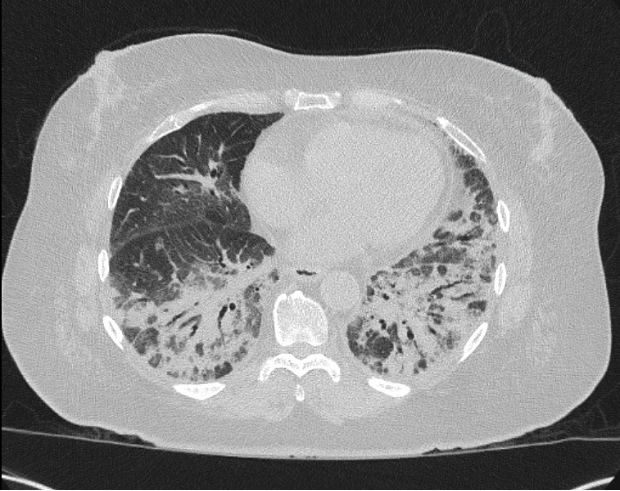

Case Presentation: A 75-year-old female with a medical history of type II diabetes mellitus, asthma, and arthritis presented with approximately three months of recurrent pneumonia. On admission, she complained of progressive generalized weakness with associated shoulder pain, shortness of breath, cough with foul-smelling sputum, and new, bilateral wrist swelling. Vital signs were significant for tachypnea and a fever (100.6 F). Initial complete blood count (CBC) was notable for anemia (Hgb 9.6, HCT 29.6) and leukocytosis to 12.2. Repeat CBC on day three of admission was significant for eosinophilia (eosinophil # 1.0, % eosinophil 6.6) with elevated c-reactive protein (CRP) to 101.9 and erythrocyte sedimentation rate (ESR) to 56. Chest X-ray showed likely multifocal pneumonia, and chest computed tomography (CT) scan showed worsening basilar predominant consolidation when compared to scans from a month prior when she was hospitalized for dyspnea (Figure 1). Given that she previously completed multiple courses of antibiotics (azithromycin, amoxicillin/clavulanate, levofloxacin, linezolid) and appeared clinically well, empiric antibiotics were held. Two days into her admission, she developed a diffuse, pruritic rash along her arms, legs, and buttocks that she attributed to recent use of antibiotics. A skin biopsy showed urticarial vasculitis. Infectious workup, including fungal and parasitic studies, were negative. Lung biopsy was consistent with an organizing pneumonia. Given these findings, there was concern for an underlying rheumatologic process that prompted consultation and extensive rheumatological workup. While the bulk of this workup was also negative, the myositis panel returned positive for PL-12 antibody. She was ultimately diagnosed with anti-synthetase syndrome. In close consultation with the pulmonology and rheumatology teams, the patient was pulse dosed with 1-gram solumedrol daily for three days. She was discharged on 60 mg prednisone for four weeks, with scheduled follow-up with pulmonology, rheumatology, and dermatology.